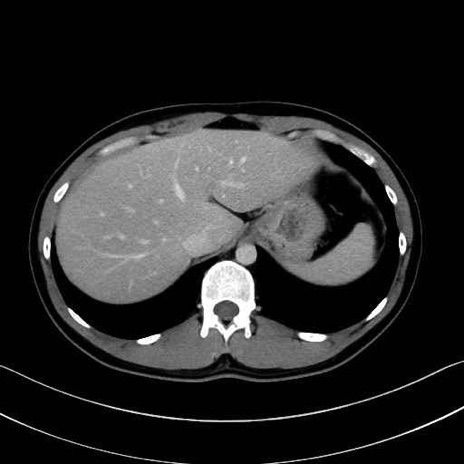

【症例】20歳代 男性 スクリーニング

■起始:典型的には腹腔動脈幹(celiac trunk)から左胃動脈・総肝動脈とともに三分岐し、脾動脈は左後上方へ向かう。

■走行:膵上縁または膵実質背側を蛇行しながら左方へ進み、膵尾部近傍で脾門へ至る。蛇行の程度は個体差が大きい。

■終枝:脾門部で複数の終末枝に分かれ、上極・下極枝や脾門枝群を形成する。胃短動脈群や左胃大網動脈はしばしば脾動脈から分岐する。